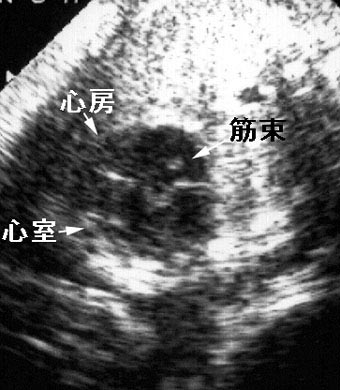

無脾症候群

心房と心室はそれぞれ単心房と単心室を示す。心房内に異常筋束を認め、無脾症候群が疑われる。